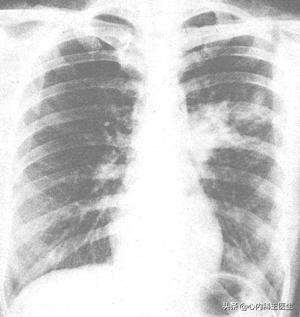

肺部影像学表现

肺部胸片检查肺炎支原体肺炎可表现为小斑片状影,大片状密度增高影以及肺部絮状阴影等。